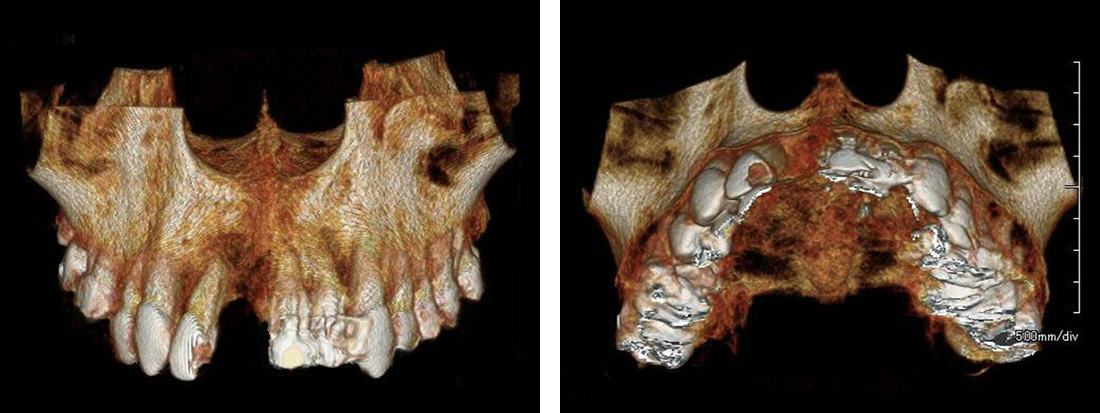

1.診査・診断

レントゲンなどによって十分な診断の後、インプラント治療に関する説明を受けます。インプラント治療は専門のトレーニングを受けた歯科医師のみが行います。

レントゲンなどによって十分な診断の後、インプラント治療に関する説明を受けます。

インプラント治療は専門のトレーニングを受けた歯科医師のみが行います。

2.インプラントを埋め込む

CT事前にシュミレーション

シュミレーション通りにインプラント埋入